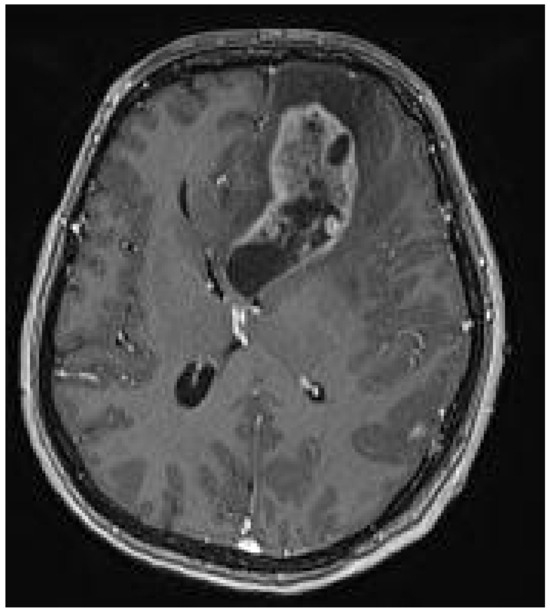

Association of Schimmelpenning Syndrome with Astrocytoma (WHO Grade 3): Case Report

2. Case Presentation

Tumova, A.; Auslands, K.; Millers, A.; Priede, Z.; Buks, M.; Ozola, A.; Ozoliņa, E.; Bicāns, K.; Ulmanis, R. Association of Schimmelpenning Syndrome with Astrocytoma (WHO Grade 3): Case Report. Medicina 2024, 60, 1688. https://doi.org/10.3390/medicina60101688